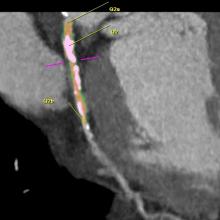

Web Stayman, Ph.D., Johns Hopkins University, presents an overview of research he presented at the 2012 American Association of Physicists in Medicine (AAPM) annual meeting in Charlotte, N.C. It involves an iterative technique for computed tomography (CT) to better contend with implants to improve image-guided surgery or interventions. The technique takes knowledge about the components and integrates it into the reconstruction to eliminate artifacts.